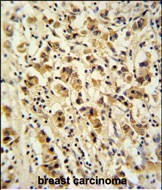

IHC 1/100-1/500 Human,Mouse,Rat

Antibodies targeting DDX49 are essential tools for studying its expression, localization, and molecular interactions. They enable detection via techniques like Western blotting, immunofluorescence, and immunoprecipitation, aiding in the exploration of DDX49’s role in ribosome assembly and RNA homeostasis. Research suggests DDX49 may contribute to pathological conditions, including viral infections (e.g., HIV-1) and cancers, where dysregulated RNA processing drives disease progression.